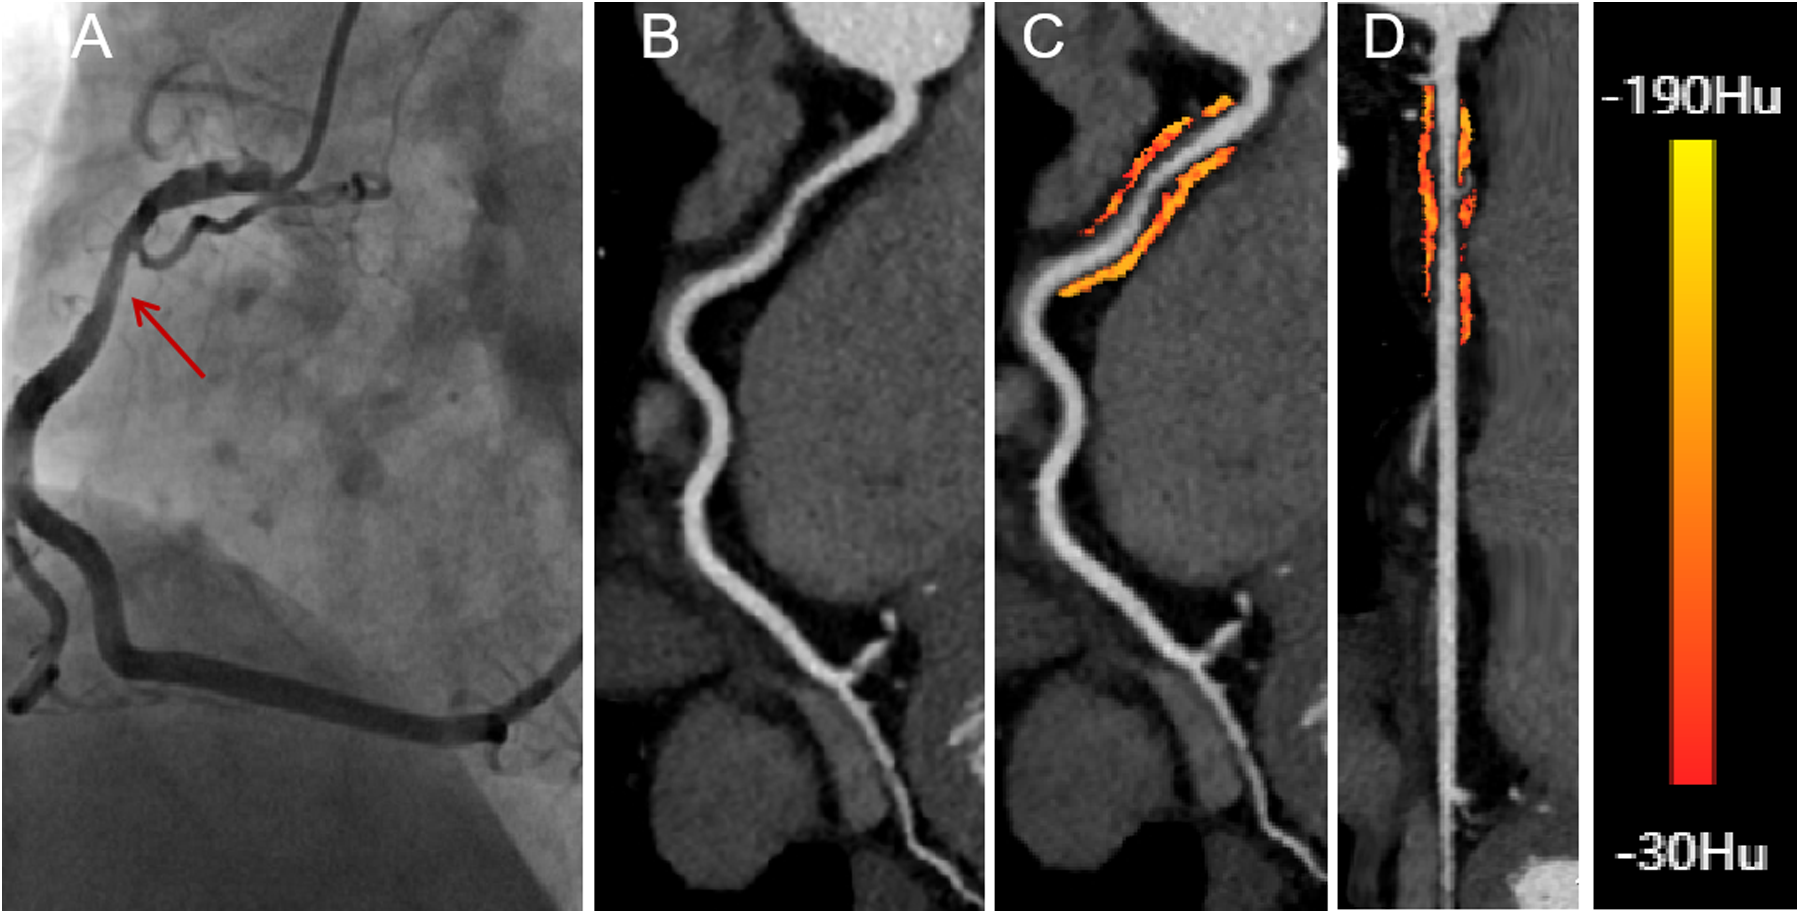

Figure 3

A 58-year-old male presenting with significant hemodynamic stenosis in the proximal segment of the right coronary artery. (A) The red arrow shows a 70% lumen narrowing in the DSA. (B) CCTA with curved planar reformation demonstrates non-calcified plaque formation in the proximal segment of the right coronary artery. (C) A representative curved planar reformation image reveals a FAI [−73 HU] of PCAT, indicative of ischemic coronary artery narrowing. (D) FAI color maps of the PCAT in the proximal 10-50 mm of the right coronary artery, with a probe straightening image. CT attenuation values color spectrum from red [−30 HU] to yellow [−190 HU]. CCTA, coronary computed tomography angiography; DSA, digital subtraction angiography; FAI, fat attenuation index.

The PCAT volume and FAI were calculated for the proximal 10–50 mm of the RCA and the proximal 0–40 mm of the LAD and LCX arteries. For the RCA, the first 10 mm of PCAT was excluded to minimize partial volume effects and artifacts caused by intraluminal contrast (25). In cases where the RCA length was less than 50 mm, the proximal limit of PCAT measurement was adjusted to within 0–10 mm of the RCA orifice. Coronary branches of the RCA and adjacent myocardial tissue were excluded from the automated PCAT analysis to avoid confounding factors (24).